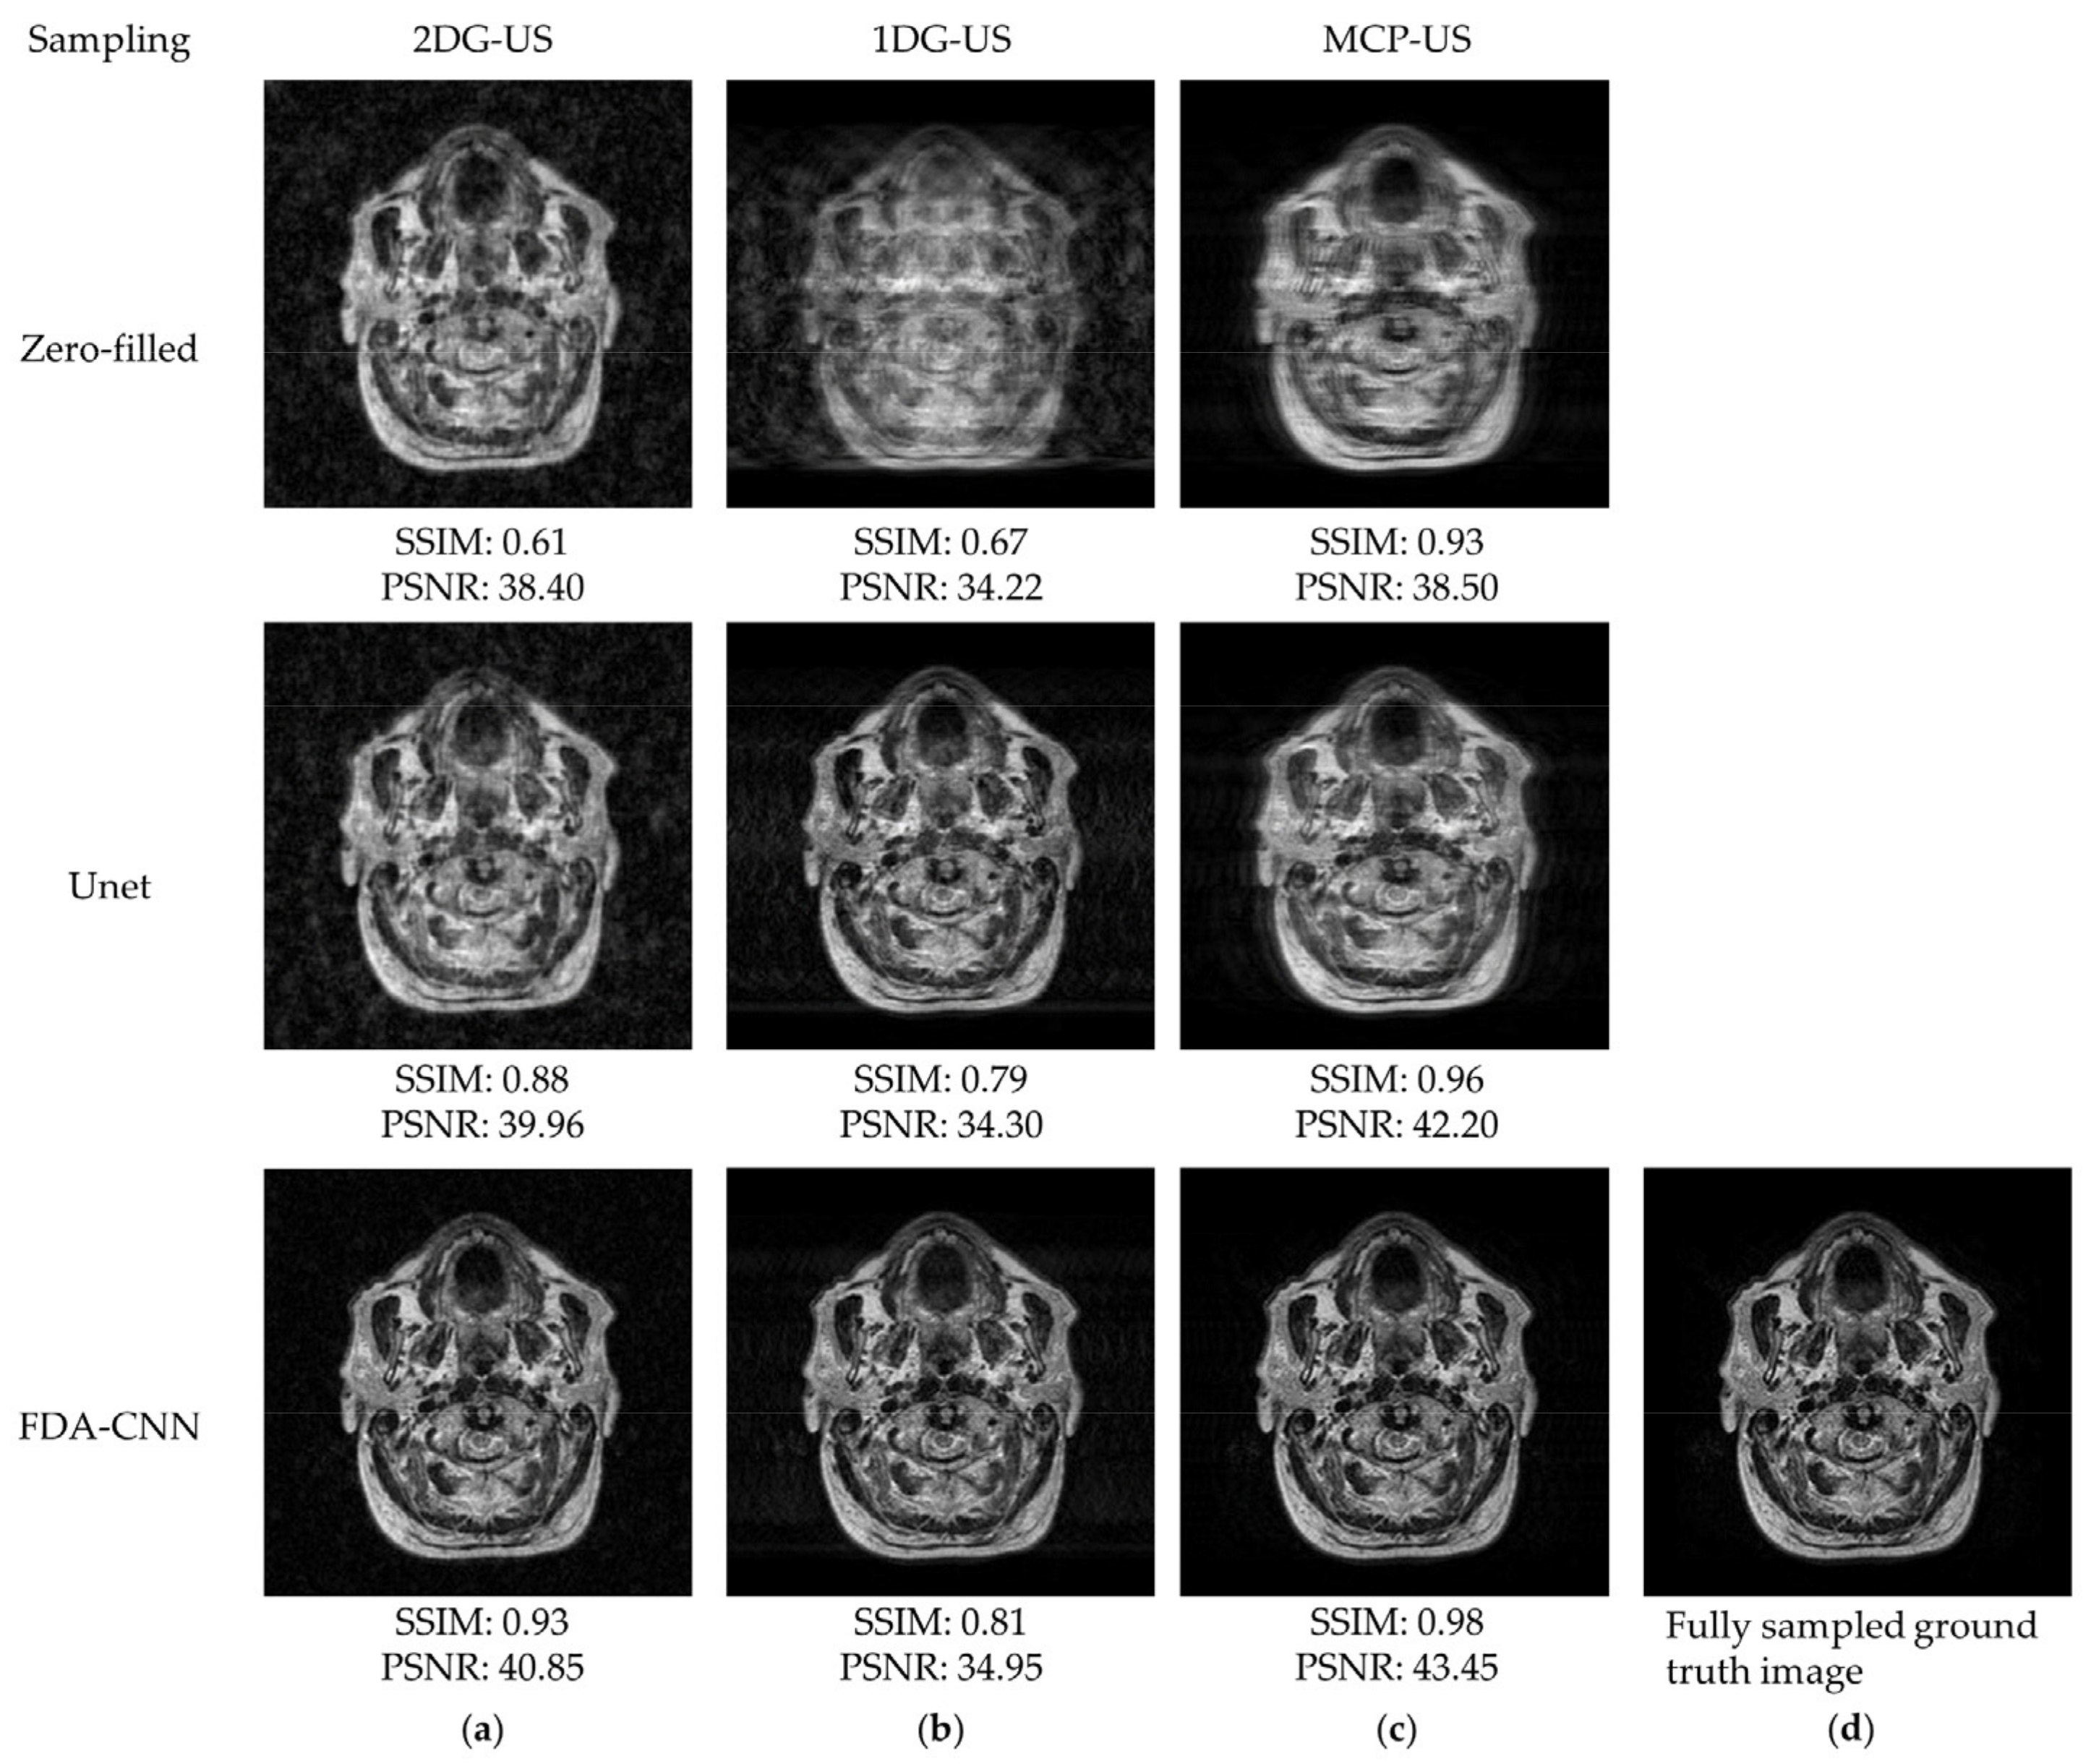

4.2. FastMRI and IXI Datasets